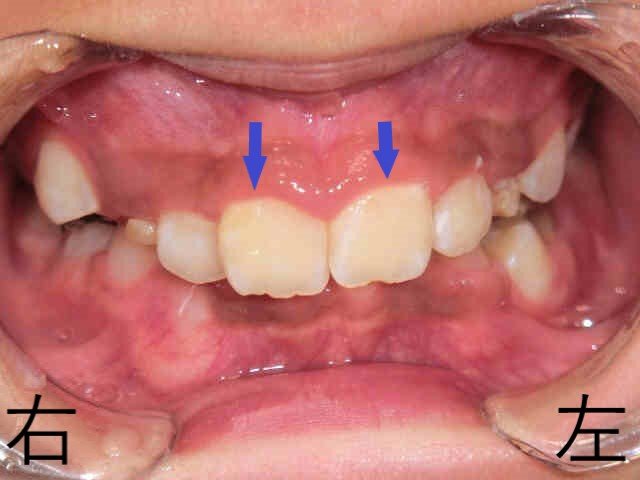

こちらは小児矯正治療を開始する前、10歳6か月の女児の噛み合わせを撮影したものです。

上の前歯に隠れてしまい、下の前歯がほとんど見えない状態でした。

噛み合わせが深い“ディープバイト”という状態で、最近の子どもさんに多く見られる噛み合わせの一つです。

この患者様も、笑った時に上の前歯しか見えず、唇に力を入れないと口を閉じにくい状態でした。